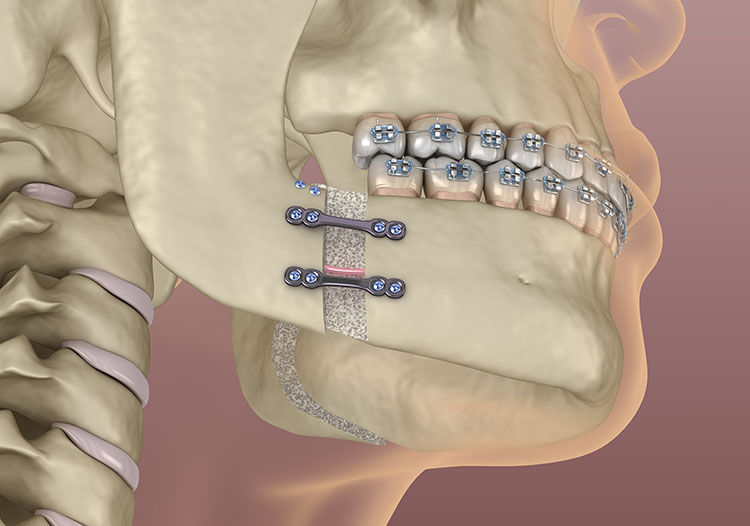

20 Minimally Invasive Orthognathic And Condylar Surgery | Pocket Dentistry

pocketdentistry.comcondylar orthognathic surgery minimally invasive pocketdentistry

pocketdentistry.comcondylar orthognathic surgery minimally invasive pocketdentistry